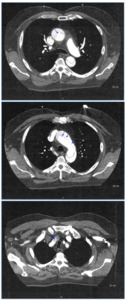

An electrocardiogram was ordered which revealed normal sinus rhythm with normal PR, QRS, and QTc intervals. A CT chest angiography was carried out due to high index of suspicion of aortic dissection. Imaging confirmed a Type A aortic dissection extending from the aortic root to the upper abdominal aorta, with the dissection flap extending into the brachiocephalic, left common carotid, and left subclavian arteries. There was also evidence of trace hyperdense pericardial fluid, especially adjacent to the ascending aorta, suspicious for trace hemopericardium [figure 1].